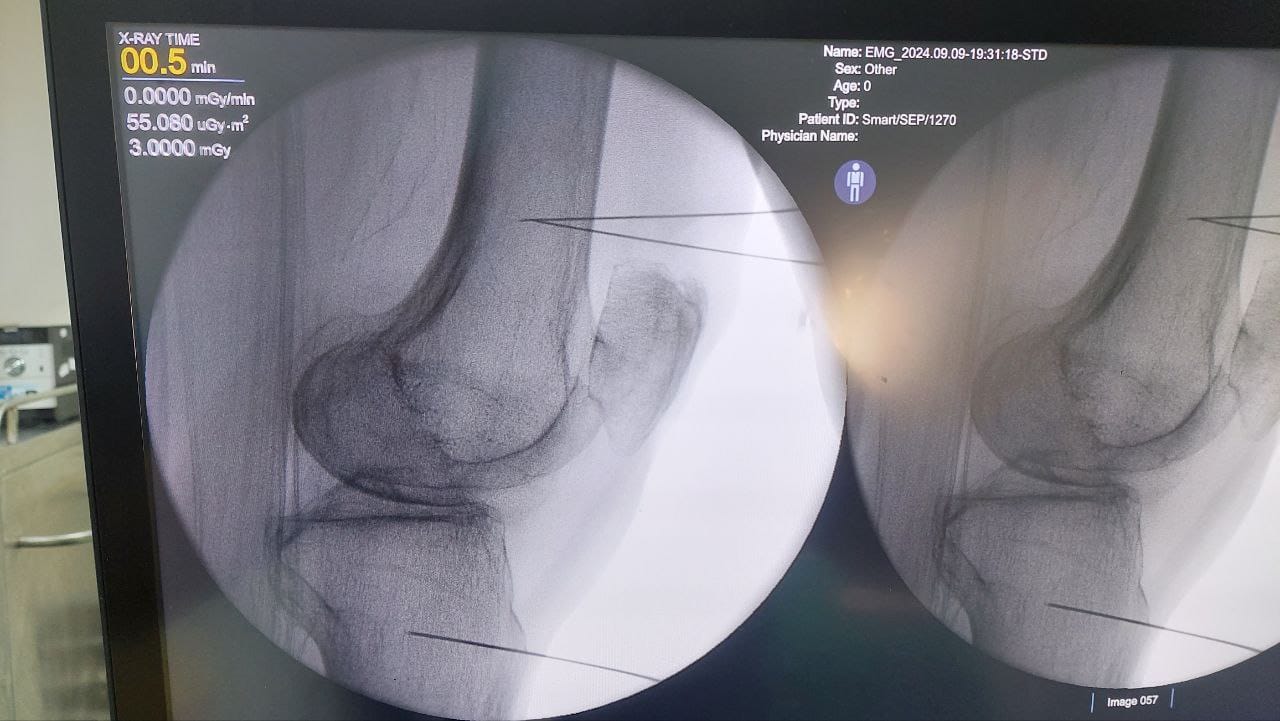

Procedures

Struggling with chronic pain? Get advanced, personalised pain management from Dr. Manish De, one of Kolkata’s leading pain specialists. From knee pain, heel pain, low back pain, frozen shoulder, migraines, cancer pain to post-TKR persistent pain—Dr. De offers safe, evidence-based treatments across multiple locations: